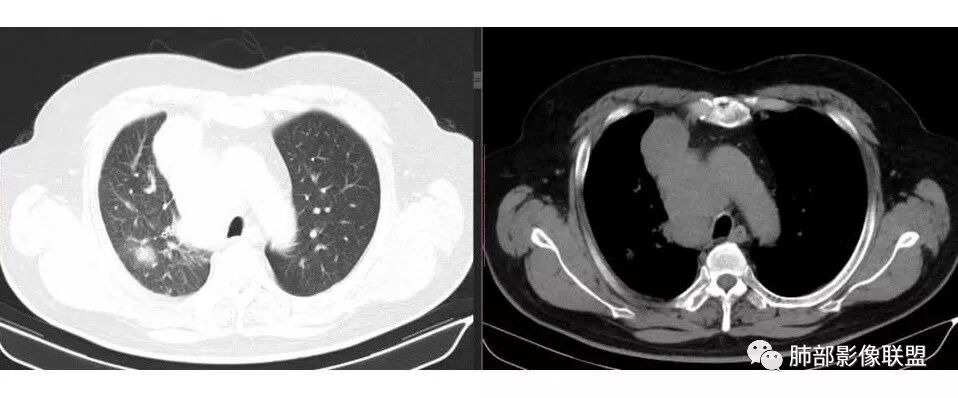

1.右肺上叶不规则结节影,右肺门及纵隔多结节并形成巨大块影,密度均匀,沿途支气管明显狭窄。

原发灶小或隐匿,肺门纵隔淋巴结异常增大,所谓“娘小崽大”常见于肺小细胞癌!

2.右肺小叶间隔增厚伴微小结节,提示癌性淋巴管炎。